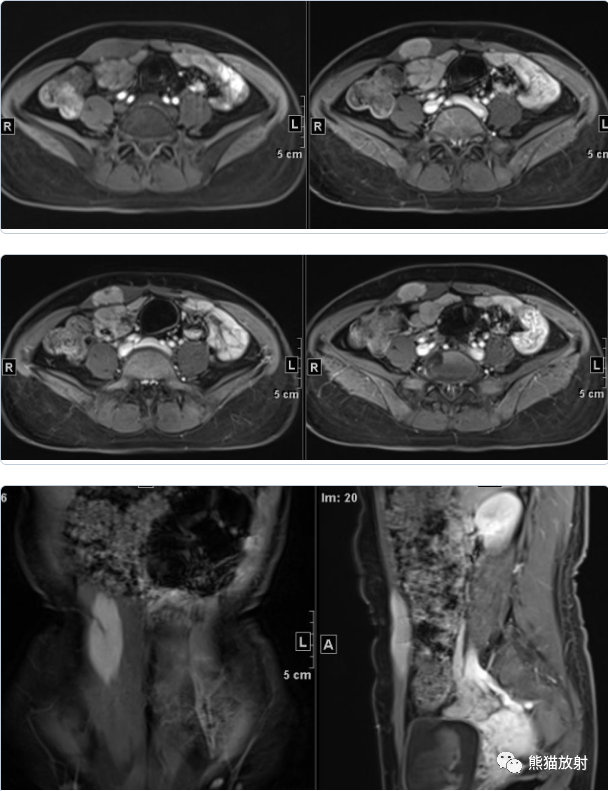

女41岁,腹壁肿物。

最后诊断: 韧带样纤维瘤

2、DTF形态较规则,以膨胀性生长为主,呈梭形或椭圆形,病灶沿着肌筋膜生长,矢状位显示本例病灶与肌肉长轴一致;

3、病灶边界多较清楚,也可浸润腹壁肌肉(筋膜尾征-较特征性表现)和皮下组织,或跨肌间隙,与腹膜、腹腔脏器粘连;

4、密度较均匀,很少见到坏死、钙化或者液化;

5、DTF信号特点及其不均匀性与病灶内组织学成分的比例和分布有关:细胞成分多的区域T2WI信号较高,胶原纤维多的区域T2WI信号较低;

6、病灶内各序列见条带状低信号影,无明显强化,病理为致密胶原纤维化和少细胞区,是 DTF较特征性的表现。